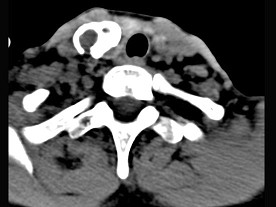

5.男性,40歲,頸部出現(xiàn)無(wú)痛性囊性包塊2年余,CT掃描如圖所示,最可能診斷為  (    )

正確答案:A